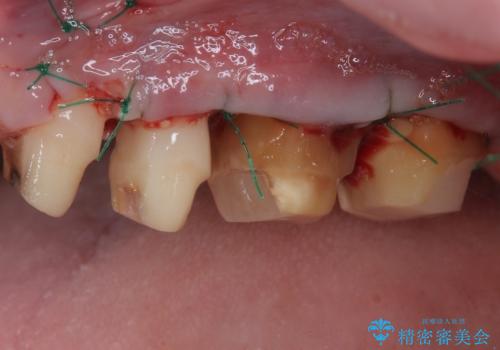

- かかりつけ医にて歯周病治療の名目で治療を行っていたものの、治療プランが明確でないままにインプラント処置を行うとことに疑問を感じ、来院された患者様です。

かかりつけ医では、歯周病治療は終了したため、抜歯を行った右上奥歯にインプラント埋入を行うとの案内があったそうです。

検査を行ったところ、歯周外科処置や抜歯が必要と思われる箇所が散見されたため、あらためて当院に歯周病の初期治療から行うこととしました。